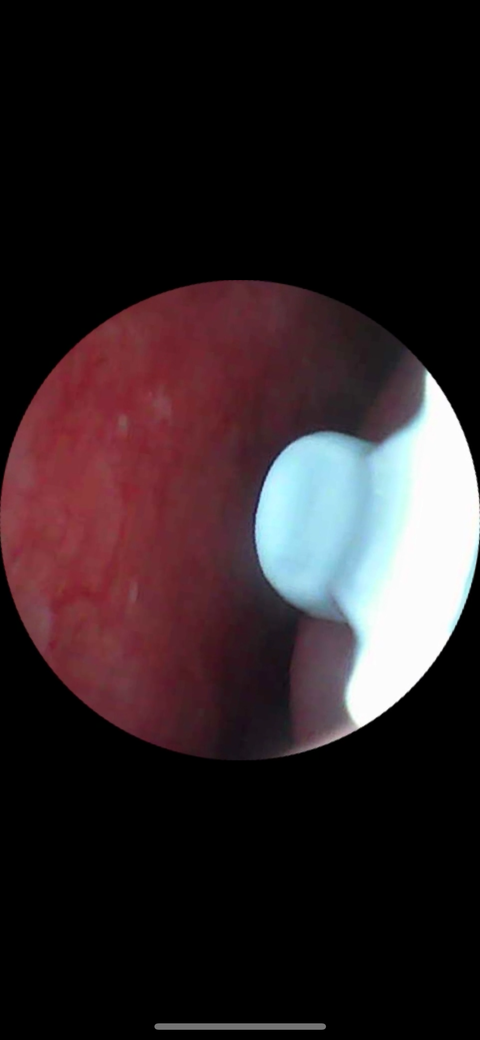

비중격만곡증 교정술, 하비갑개 축소술을 받은 지 2달이 지났습니다. 현재 왼쪽 코 비중격 쪽에 건조감이 계속 느껴집니다. 코세척과 식염수 스프레이를 써도 차도가 없네요. 비중격쪽에 혈관이 살짝 보이는데 이것 때문인가요? 혹시 이게 염증이거나 그런 걸까요?

• 1번 째 사진

안녕하세요. 이송재 의사입니다. 올려주신 사진과 말씀하신 증상은 관련성이 떨어집니다. 빈코증후군의 대표적인 증상은 코막힘 입니다. 건조한 날씨로 인해서 건조감이 생긴 것으로 생각 됩니다.